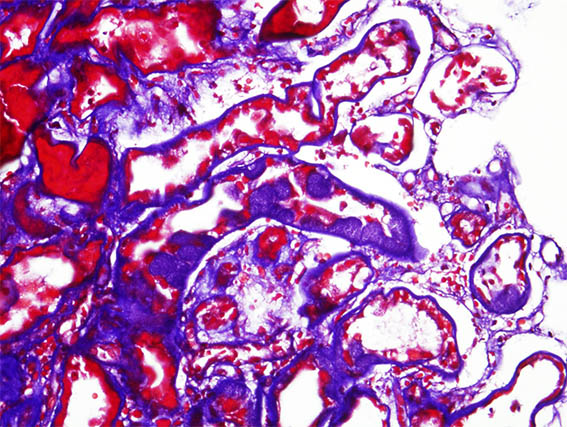

Una paciente de 41 años con diabetes mellitus de larga evolución desarrolló síndrome nefrótico abrupto, por lo que se le realizó una biopsia renal. La biopsia muestra nefropatía diabética avanzada sin GN superpuesta.

En una zona se identificaron lesiones tubulares como las que se ven en las siguientes imágenes:

Figura 2. Tricrómico de Masson, X400.